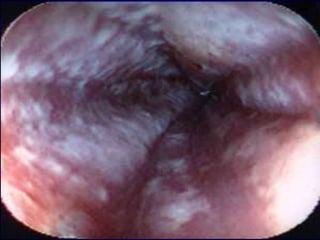

CANDIDÍASEPATOGÊNIA: Mucosa oral (estomatite ou sapinho) – placas brancas, isoladas ou confluentes, aderentes à mucosa, com aspecto membranoso, rodeadas por halo eritematoso.  Pacientes gravemente enfermos e recém-nascidos de mãe com candidíase vaginal.  Amanda

Candidiaseem mucosasMucosa vaginal – lesões semelhantes à boca com corrimento.Pacientes grávidas, diabéticas ou com terapêutica antimicrobiana prolongada.No homem = balanite (infecção da glande) como DST.  Mucosa cutânea – lesões eritematosas, crostosas e com exsudatos.Amanda